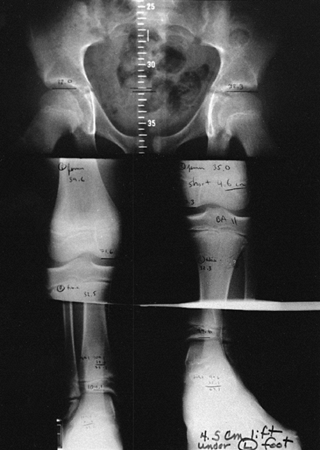

semierect, with the short side blocked up beneath the foot to level the

pelvis. Separate images are then taken of the hips, knees, and ankles,

including the plantar portion of the foot (Fig. 170.10).

The semierect position has the advantage of mimicking the upright

weight-bearing position, leveling the pelvis for more accurate

measurement, limiting patient motion between exposures, and allowing

evaluation of the contribution of the foot to the discrepancy. The only

disadvantage is that a tilting x-ray table is required.

![]() |

|

Figure 170.10.

The semierect scanogram method. The tilt table allows for placement of lifts for leveling the pelvis, and will give more accurate information about joint and length changes with weight bearing. The three images of the hips, knees, and ankles are taken in the same way as with the supine technique shown in Figure 170.7. |